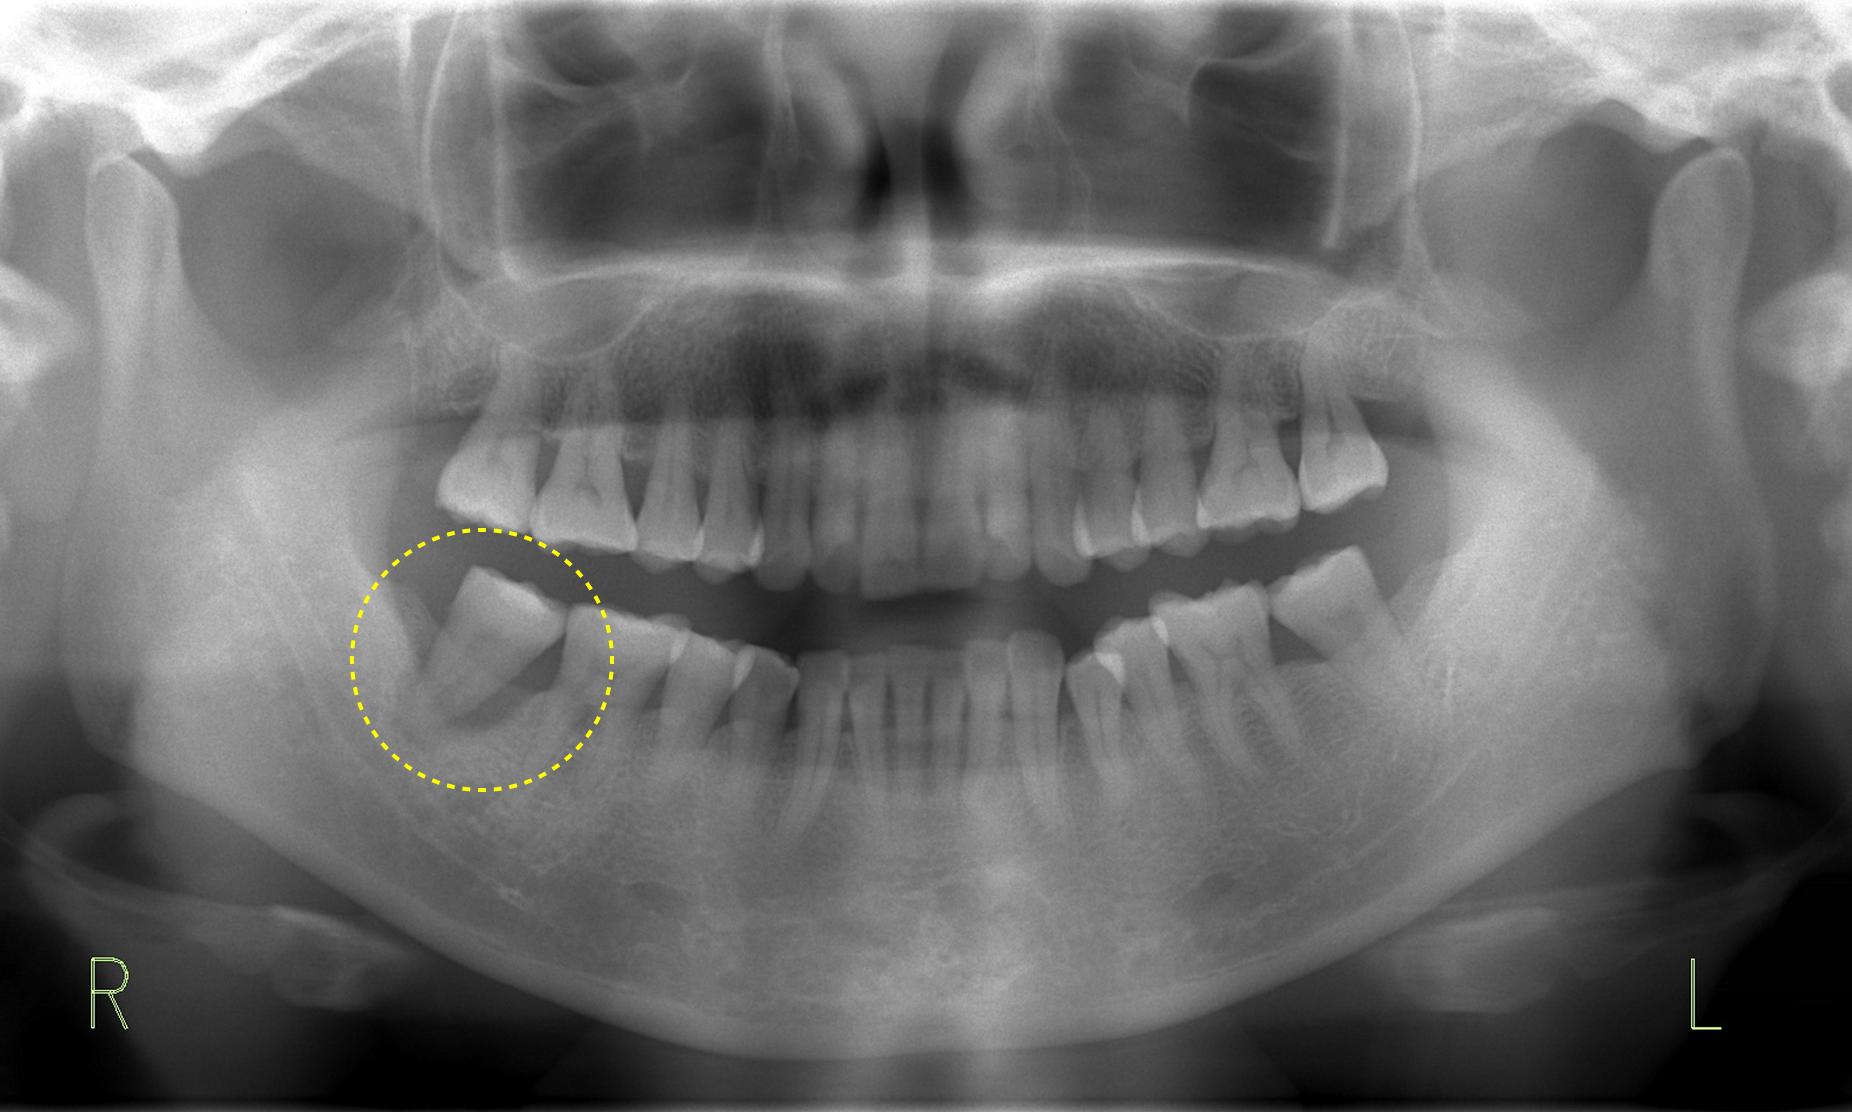

お口の中は全体的に良好な状態に見えましたが、下の奥歯に「限局型慢性歯周炎(ステージ3 グレードC)」が判明し保存が極めて難しい状態に。ここから歯周組織再生療法による回復を試みました。